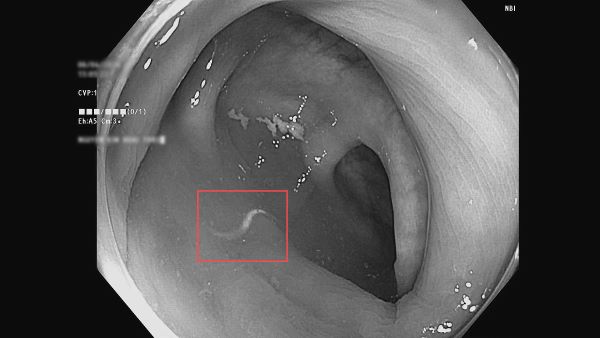

- Ký sinh trùng: Hình ảnh nội soi phát hiện có giun đang di chuyển trong lòng đại tràng.

- Đa polyp: Xuất hiện 4 khối Polyp kích thước từ 0,3 – 0,6 cm tại vùng đại tràng Sigma và trực tràng.

- Chẩn đoán: Viêm đại trực tràng, nhiễm ký sinh trùng và đa polyp.

Theo BS. Nguyễn Huy Thông, nhiễm giun gây thiếu máu mạn tính là nguyên nhân thầm lặng dẫn đến tình trạng chóng mặt, suy nhược. Đặc biệt, các khối polyp nhỏ nếu không được xử lý sớm sẽ tăng kích thước và tiềm ẩn nguy cơ ung thư rất cao.